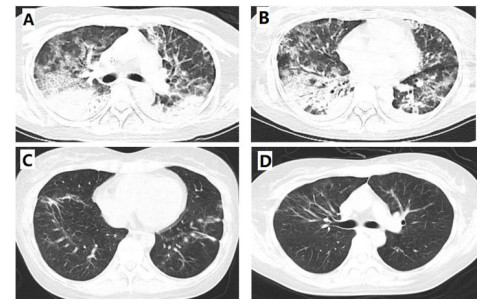

第一次收住院诊疗经过:完善常规生化提示低钾血症、高脂血症,超声心动图:微量心包积液,EF67%。肺通气功能正常。库欣综合征定性定位诊断方面,血总皮质醇(血F)(8AM) 69.6 μg/dL, ACTH(8AM) 664.0 pg/mL, 24 h尿游离皮质醇(24HUFC)2 723.2 μg/24 h,大剂量地塞米松抑制试验(见表 1); 标筛查:AFP 4.6 ng/mL, CA19-9 22.2 U/mL, CEA 3.0 ng/mL, CA125 38.4 U/mL, 细胞角蛋白19片段Cyfra211 6.0 ng/mL, CA242 19.0 U/mL, CA72-4 8.6 U/mL, CA15-3 12.9 U/mL, ProGRP 26.0 pg/mL, NSE 15.4 ng/mL。生长抑素受体显像:前纵隔结节,生长抑素受体高表达灶,考虑神经内分泌肿瘤可能性大;双侧肾上腺增生。(图 1C);垂体平扫+动态增强MRI:垂体后叶短T1信号存在垂体左翼强化减低区,考虑微腺瘤。胸增强CT:前纵隔占位,结合病史,不除外异位ACTH瘤(图 1A);TB细胞亚群11项: %memory T4 78.1%, B% 17.9%, T4% 17.6%, T8% 42.1%, RAT4% 21.9%, NaT4% 21.7%, 28T8% 32.1%, DRT 8% 76.2%, 38T8% 83.0%, T4/T8 0.42%, 垂体前叶功能,甲功1:TSH 0.077 μIU/mL, FT4 1.73 ng/dl, FT3 2.17 pg/mL, GH < 0.05 ng/mL, IGF1 132 ng/mL。FSH 2.13 IU/L, LH 0.26 IU/L, E2(Ⅱ) < 15 pg/mL, T 1.96 ng/mL, PRL 6.9 ng/mL, P 5.31 ng/mL。MEN筛查,GASTRIN 260 pg/m,ProGRP 23.9 pg/mL。降钙素(CT) < 1.5 pg/mL,钙素原PCT 0.23 ng/mL, CK 33 U/L。IPSS+DDAVP兴奋试验示基线时中枢和外周ACTH无梯度(见表 2),结合大剂量地塞米松抑制实验不被抑制,支持异位ACTH综合征,考虑胸腺占位为责任病灶可能。治疗方面,入院后予口服及静脉补钾、螺内酯纠正低钾血症,监测血糖,餐后2 h血糖高,给予胰岛素及口服降糖药后血糖基本达标。患者前纵隔结节考虑为异位ACTH瘤可能大,2020-08-26行VATS胸腺及肿瘤切除术,术后恢复良好,激素替代方案由围术期静脉应用琥珀酸氢化可的松逐渐过渡为醋酸氢化可的松片早40 mg,晚20 mg替代治疗后出院(图 3主要指标趋势及用药情况)。2020-08-31无明显诱因出现发热,体温最高达39℃,当地诊所静点“头孢类抗生素”、口服布洛芬治疗2 d,仍间断发热,并出现站立后头晕,当时血压76/40 mmHg,就诊当地医院,查血常规:WBC 6.01×109/L, NEUT% 85.2%, LYM% 13%; CRP 194.74 mg/L; CMV DNA阳性;胸部CT提示双肺弥漫渗出,考虑“重症肺炎I型呼吸衰竭”于当地重症监护室予以“无创呼吸机辅助呼吸,哌拉西林他唑巴坦、奥司他韦、伏立康唑抗感染,丙种球蛋白免疫支持”。治疗效果欠佳,胸闷、憋气逐渐加重,伴咳少许白色黏痰。2020-09-03就诊本院,考虑重症肺炎收入急诊重症监护病房,第2次收住院诊疗经过:呼吸方面:复查胸CT提示:双肺弥漫炎性改变,双侧胸腔积液并左下肺轻度膨胀不全(图 2A 、B)。予高流量氧疗支持,完善肺泡灌洗液: PCP DNA阳性(+),CMV(+),结合病史、症状、体征及辅助检查证据,考虑肺孢子菌肺炎、巨细胞病毒肺炎、混合细菌感染,头孢他啶1 g/8 h、莫西沙星0.4 g/d、TMP/SMX 3片3次/d,更昔洛韦0.25 g/8 h,呼吸困难逐渐改善,复查CT病灶明显吸收(图 2C 、D)。内分泌方面:考虑EA导致CS术后,激素替代治疗中合并机会性感染,调整治疗:停用口服,给予琥珀酸氢化可的松50 mg/6 h。口服降糖药控制类固醇糖尿病,口服碳酸钙片治疗骨质疏松。原发病方面:结合病理胸腺病灶考虑内分泌来源类癌,恶性程度低,无需放化疗。2020-09-30出院时患者无发热、头晕、纳差、恶心、呕吐、电解质紊乱、低血糖等肾上腺皮质功能不全表现,氢化可的松早40 mg-午20 mg逐渐减量(图 3主要指标趋势及用药情况),激素替代期间TMP/SMX 2片/d预防感染,门诊随诊。

| 图 2 9-4 A、B双肺间质弥漫性渗出伴炎性改变,双下肺实变影9-16 C、D治疗后复查双肺炎性改变较前明显改善 |

并发症评估处理:该患者目前突出的表现为中-重度低钾血症,考虑为大量皮质醇激动盐皮质激素受体所致。密切监测血钾,积极纠正低钾血症,警惕低钾血症所致的心律失常、横纹肌溶解。患者首次住院期间出现严重低钾血症,经过大量的口服及静脉补钾增加钾的摄入,螺内酯保利尿剂增加钾的重吸收,具体剂量及治疗反映详见图 3,是保障患者尽快诊断及治疗的重点难点所在。皮质醇血症可导致糖脂代谢、水盐平衡异常,可通过监测血糖、HbA1c、糖化白蛋白、容量管理等动态调整,有研究表明,液体负平衡可降低重症肺炎患者病死率[5]。钙磷代谢方面,长期高皮质醇血症可促进尿钙排泄、抑制肠钙吸收,导致继发性骨质疏松,因此骨密度、胸腰椎正侧位等检查及积极补钙等治疗是预防骨质疏松防止骨折的关键。通过完整的定性定位检查及手术病理证实为前纵隔类癌的EA所致CS,整个病程相对较长,虽手术过程顺利,但术后激素替代过程中很快出现了机会感染,结合图 3趋势不难发现,患者术后ACTH及血F水平急剧下降,淋巴细胞绝对值也低于正常下限,当内源性激素水平迅速下降的同时,外源性激素补充不及时可能出现皮质功能不全表现,且患者体内长期处于高皮质醇水平,加之手术打击,再次发热后迅速出现多种机会病原体感染,PCP及巨细胞病毒(cytomegalovirus,CMV),内环境紊乱、皮质功能不全进展为休克,病情危重,病死率极高,因此,机会性感染的早期识别、合理的抗感染方案及容量管理策略至关重要[6]。

2.3 为什么药物控制或手术切除肿瘤后患者容易发生机会性感染?Arlt, A报道的右肾神经内分泌肿瘤患者在接受甲吡酮和氢化可的松治疗,皮质醇水平下降后肺泡灌洗液发现PCP,虽加用预防性复方磺胺甲恶唑治疗仍迅速进展为呼吸衰竭死亡[7],Graham等[8]曾报道6例内源性库欣综合征合并机会性感染,感染风险与皮质醇水平相关,Sarlis等[9]回顾性分析发现,当皮质醇水平下降过程中继发重症PCP感染,可能与氢化可的松的抗炎作用减低有关;van Halem等[10]系统回顾了库欣合并PCP感染患者,发现在开始应用肾上腺抑制剂如酮康唑、米托坦或糖皮质激素受体拮抗剂如米非司酮等治疗使皮质醇水平下降时,在激素替代的免疫重建过程中也容易继发PCP等机会感染,Hasenmajer等[11]在近期的一篇库欣综合征与免疫的综述中提到,当通过药物或手术使患者库欣得到缓解时,患者体内淋巴细胞计数会随之下降,可能与过程中影响骨髓造血、细胞因子变化及免疫细胞凋亡相关,进而使机会感染风险增加,这点与本文患者表现一致(图 3)。另文献报道,当24 h尿UFC超过5倍上限或血皮质醇水平超出正常上限20倍时,或者治疗后存在激素水平急剧下降时,此时建议经验性加用复方磺胺甲恶唑预防机会性感染[12]。